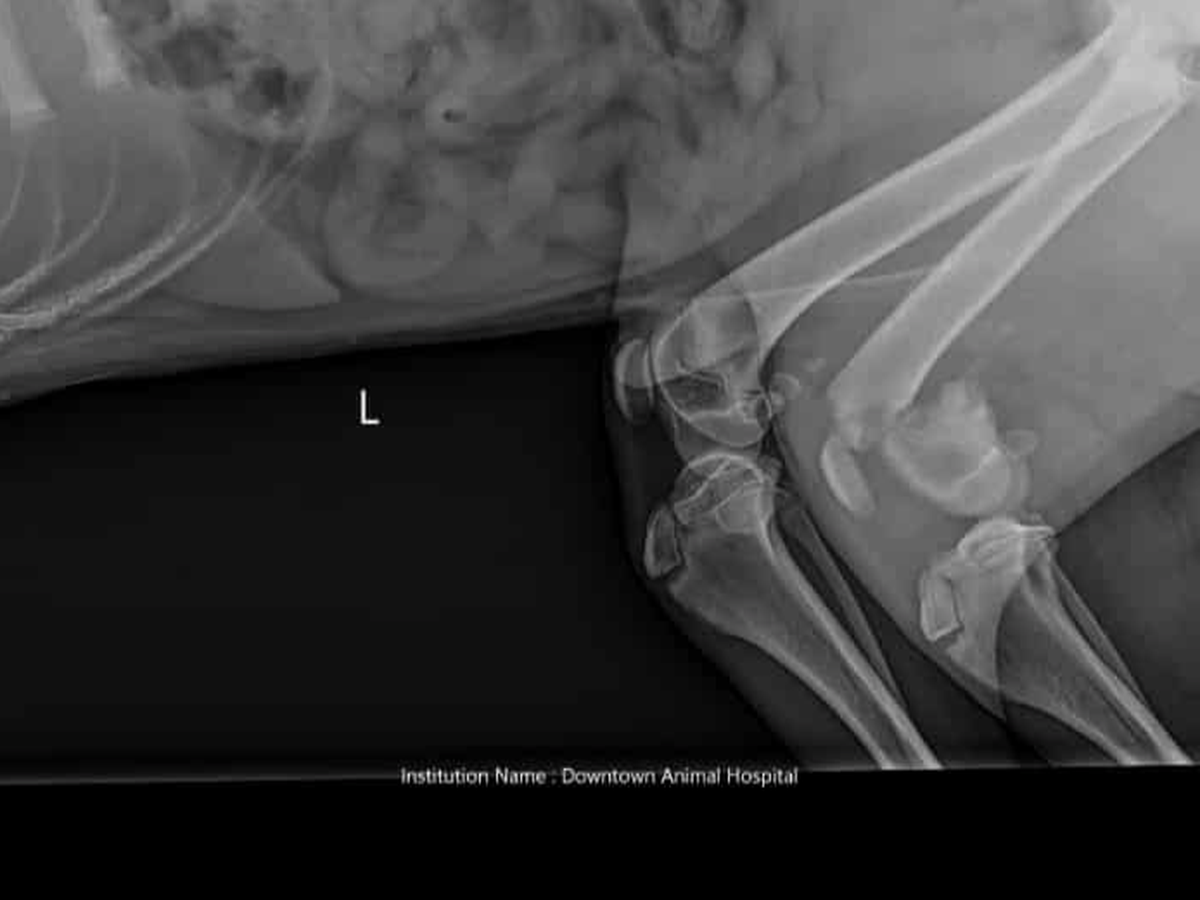

After numerous strokes left his father paralyzed Donald and his partner Missy needed to do major renovations on their home. Which was a huge financial burden that is still effecting them to this day. Their dog Joe is still just a puppy. But is currently in training to play a very important role in their lives. Donalds father has suffered over 2,000 strokes which can come on at any time. Missy, Joe's mom, also has epilepsy. He's not just a pet, he assists them in their daily lives. On Thursday an Amazon delivery driver who was unknown to them struck Joe. Thankfully no internal organs were damaged. Most of the injuries he suffered were to his leg. Joes tendons that are meant to hold his knee together are completely irreparable. The nerve endings have all been severed. His bones are broken and there's no blood flow. So it's basically dying from the knee down and needs to be removed. The estimated cost is approximately up to $7,000 or more, depending on factors that may come into play during the procedure. Amazon has been contacted. But unfortunately there were no other witnesses at the time of the incident. So the family has been left to cover the expenses. If you could please help by sharing this post or by donating anything you're able to. Joe is still young and deserves to walk and live a life without this damage. We really appreciate all the help we can get.